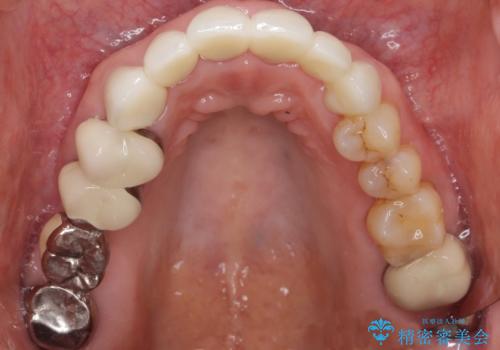

被せ物を除去したところ根管治療後の処置が不十分であったため、ファイバーコア(金属を用いない強くてしなやか材質の土台)を植立したのち、ジルコニアセラミッククラウンによる治療を行いました。

- ¥760,000 (仮歯¥10,000×6本、ファイバーコア¥20,000×5本、ジルコニアクラウン¥100,000×6本)費用は治療当時の料金となります

金属を使わないジルコニアセラミッククラウンの自然な仕上がりにご満足頂けました。

被せ物の種類:ジルコニアセラミッククラウン スタンダード